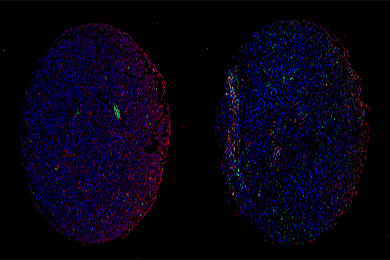

病理图像分析系统是一门先进的病理诊断系统,采用先进的图像处理技术与高精度硬件配置,从系统信号的获取、测量、处理到打印输出全部实现彩色化、自动化、智能化,具有操作简便、图像处理功能强、图像分析智能化、图像清晰度高、图文报告打印快捷、数据库管理功能强大等优点。